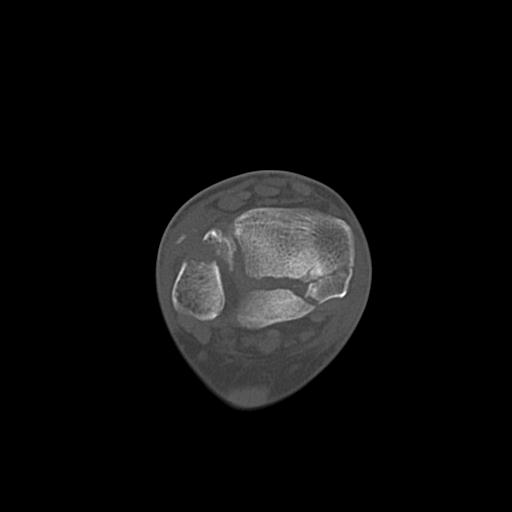

49554 3/13 膝 4R 3/16 4R 1/18 2R 78歳男性 膝蓋骨骨折